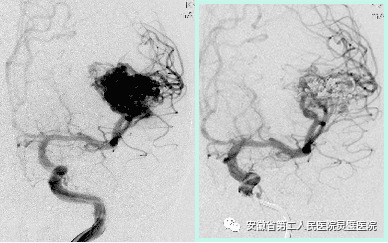

三、脑血管病的综合治疗技术

脑血管病亚专业组紧跟国际前沿,目前全面开展颅内动脉瘤、脑动静脉畸形、硬脑膜动静脉瘘等脑血管病的外科及血管内治疗,尤其对复杂颅内动脉瘤,灵活运用支架及球囊辅助、双微导管、液态栓塞剂栓塞、覆膜支架等技术,取得良好效果。开展烟雾病血管搭桥、颈内内膜剥脱术等脑血管外科手术。

前交通动脉瘤术前和术后

颈内动脉动脉瘤术前和术后

动静脉瘘术前和术后